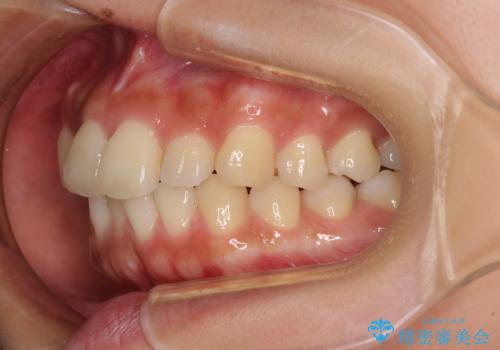

【モニター】歯列が狭くデコボコが気になる 急速拡大装置を用いたインビザライン矯正

- 奥歯の咬み合わせと治療を放置したまま奥歯を気にして来院された患者様です。

上顎骨の幅が下顎骨よりも小さいので、拡大装置により骨幅を広げて上下関係を改善し、その後インビザラインにて歯並びを整えることとしました。

上下の骨幅を改善したことで、スムーズに歯列矯正を行うことができました。

土台のまま放置されていた歯は土台の状態で咬み合っていましたが、急速拡大を行った際に咬み合わせが著しく挙上されたため、その際に土台を大きくすることで咬み合う歯との距離を確保しました。